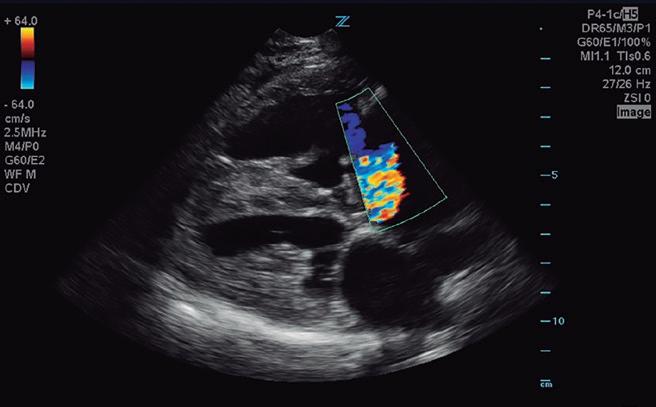

Bloqueantes de canales del calcio Hidralazina, nitratos e IECA